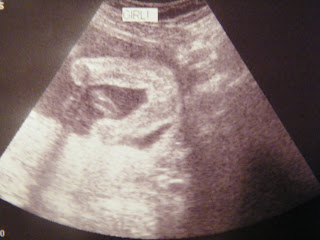

Anatomy 101

Hello all!  Kris again!  Jill is wiped out from being on the phone/computer all day so I get the honor of posting about our latest visit to the doctor.  Everything went really well today.  Jill and Scout are both doing wonderful.  We were 99% sure it was a girl after our last visit, but after today we are 100%.  Scout weighs 12 oz. and is developing beautifully.  She moves around constantly in her little home, and it was funny watching the tech try and track her down for pictures.  She has all her fingers and toes, and her organs are growing exactly as they are supposed to.  Jill has only put on 10 pounds so far and she looks beautiful as always.  We really like Dr. Stevenson.  For a quick job update......Jill is going to decide something this week.  She is down to the final two and we should know for sure by Thursday.  It will be nice to have this out of the way so that we can start enjoying this pregnancy a little more.  Please pray that we make the best decision and that Jill ends up with a company that will value her as much as her current one does.  I'm putting a couple of pictures from today below for everyone.  We appreciate all of your prayers, and we hope everyone is doing well.....P.S.  Stay tuned for our new weekly feature called Thoughtful Thursdays.  This was requested by one of our most avid followers, A. Smith :).

2. She is so cute! You can already start to see her features here. Keith and I have another sonogram in a couple of weeks and I'm hoping they get some side shots like this instead of him facing us. They get so big so fast!! Our babies will be here before we know it. :) Praying that everything works for you!